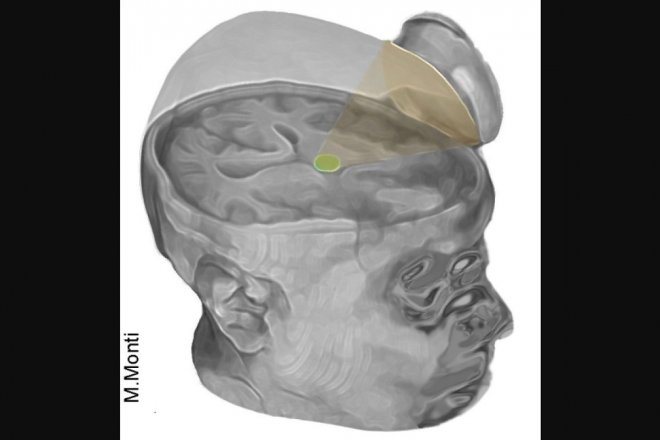

После доработки методики команда Монти провела три новых операции. Они сконструировали компактный излучатель размером со смартфон, который размещается сбоку от головы пациента. Обработка мозга излучением низкой интенсивности длится 10 минут, 10 сеансов по 30 секунд каждый. Суммарная излученная энергия меньше, чем в традиционном аппарате УЗИ, поэтому такое воздействие безопасно.